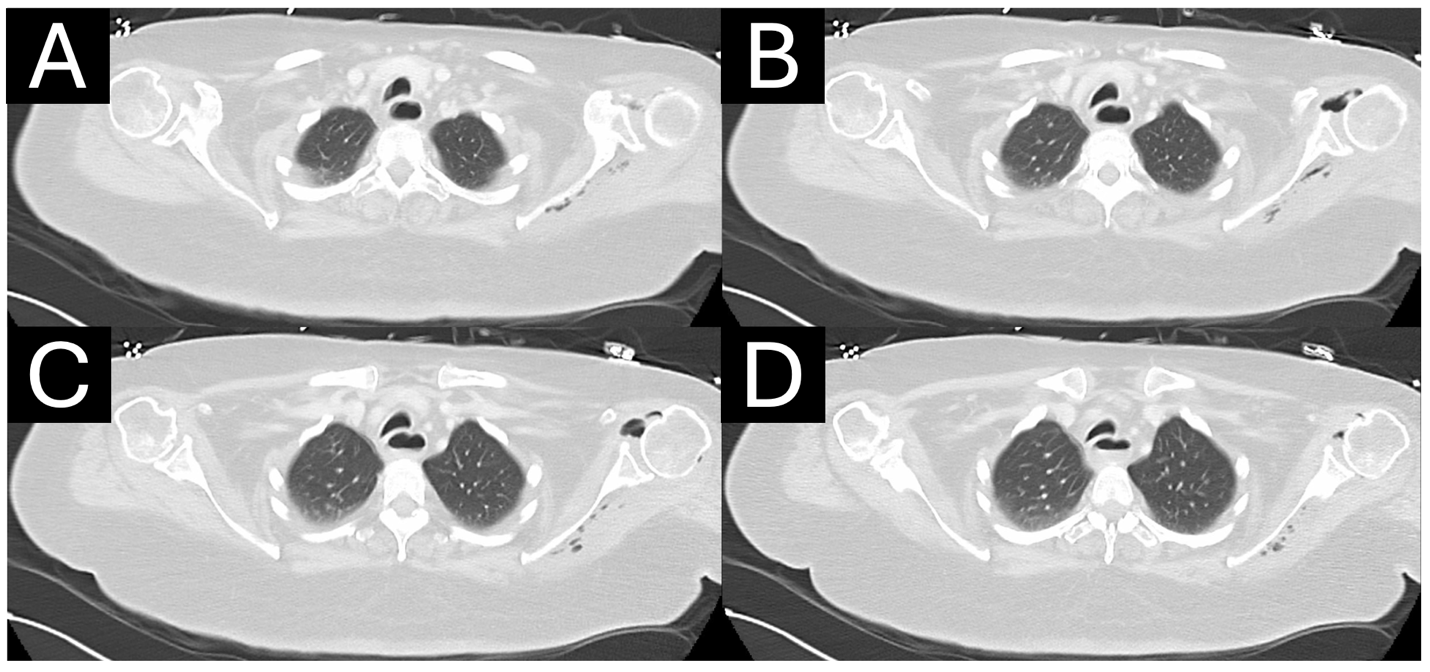

A 59-year-old, right-hand-dominant woman presented as a hospital transfer to the medical intensive care unit of an urban, quaternary academic referral center in extremis and septic shock of etiology and duration of 1 day. She initially presented to an outside emergency department from her long-term care facility with altered mental status and hypotension. Initial vital signs and laboratory values at our institution are presented in Table 1. Early diagnosis of sepsis or septic shock is crucial for prompt initiation of treatment. Time to antimicrobial therapy administration has been reported to be one of the most important interventions that decrease mortality in septic patients [10]. , vasopressin, piperacillin-tazobactam, and linezolid were administered before transfer. Zosyn and vancomycin were administered again upon arrival to our facility. The patient was observed to be in a hyperosmolar hyperglycemic state with lactic acidosis and noted to have several possible infectious sources, including a Stage IV sacral decubitus ulcer, malpositioned gastrojejunostomy tube, urinalysis demonstrating urinary tract infection (UTI) (with history of vancomycin-resistant enterococcal UTI), and chest imaging consistent with pneumonia. Computed tomography (CT) of the chest was also notable for glenohumeral pneumarthrosis with extension of deep tissue emphysema to the posterior scapular musculature concerning for necrotizing soft-tissue infection (Fig. 1a, b, c, d). The LRINEC score 8 was 9 scores of 8 or higher have been shown to be associated with NSTI, but its positive predictive value is reported to be 35% [11,12]. Given the patient’s hemodynamic instability, lack of infectious source control, LRINEC score, and imaging findings, orthopedic surgery was consulted to exclude left upper extremity NSTI.

Figure 1: (a-d) Axial computed tomography in the lung window demonstrates extensive pneumarthrosis of the left glenohumeral joint with emphysema tracking medially to the posterior scapular musculature.

NSTI is often a nexus point between critical care, acute care surgery, and orthopedic surgery due to its threat to life and limb caused by the rapid destruction of soft-tissues [7]. NSTI is a rare diagnosis, with an annual incidence of 10 cases/100,000 persons [1]. However, it has been reported to be underestimated in 41–96% of cases [4], largely due to the absence of classic signs – such as bullae, skin necrosis, crepitus, and radiographic emphysema – in over 50% of cases [4,5]. Because NSTI manifests in an extremity in up to 73% of cases [4,7], orthopedic surgery is often the first surgical service consulted. In-hospital mortality remains high, with death in up to 1 in 5 patients with NSTI, which has largely remained unchanged due to the heterogeneity of presentation, challenges of treatment, and limited high-quality evidence [2,3]. Factors associated with poorer outcomes and increased mortality include diabetes, female sex, increased age or comorbidity index, and sepsis at presentation [2,14,15], although up to 26% of patients may have no comorbid risk factors [3]. The most critical factor for improving survival and outcomes in the management of NSTI is the time to surgical exploration and debridement. A recent meta-analysis of 6051 patients with NSTI experienced lower mortality when debridement was performed within 6 hours of presentation [2]. A retrospective study of 295 patients taken for exploration for suspected NSTI revealed a negative exploration rate of 20%; however, the authors advised that surgeons accept this rate of negative exploration to avoid diagnostic delay [16]. In positive cases, rates of amputation are as high as 25% for cases in which debridement alone cannot achieve source control, reconstruction is not possible, or functional status would be superior with amputation [2,7,9]. Factors further associated with limb loss include hypotension at admission, a high glucose level (>300 mg/dL), and a high LRINEC score (>9) [17]. Our case represents a clinical conundrum and diagnostic challenge. Our patient possessed multiple factors associated with poor outcomes, limb loss, and mortality in cases of NSTI [2,13,14,16]. There was overwhelming evidence and precedent in the literature to indicate the patient for operative exploration to exclude NSTI. However, the dissection would have required debridement of the glenohumeral joint, posterior scapular musculature, and chest wall in a critically ill patient, along with a potential forequarter amputation which would have been exceedingly morbid. Although our patient had significant hemodynamic instability and septic shock requiring dual vasopressor support and broad-spectrum antibiotic coverage, laboratory abnormalities, cross-sectional imaging demonstrating deep emphysema, and a LRINEC score of 9, her physical examination was incongruous with NSTI. As demonstrated by our case, it is important to rule out other causes of intra-articular gas before proceeding with surgical exploration. Intra-articular gas or “pneumarthrosis” can be caused by traumatic arthrotomy, closed fracture or dislocation, or prior instrumentation. This patient had no history of recent trauma, and examination of her left upper extremity revealed no apparent wound that would suggest an arthrotomy (Fig. 2). In the absence of penetrating trauma, closed fracture [18,19] or dislocation [20] can cause pneumarthrosis from the vacuum phenomenon of nitrogen gas exchange with distraction or expansion of a closed space [21]. There was no evidence of closed fracture radiographically (Fig. 3a and b), and her glenohumeral joint was concentric on axial CT (Fig. 1a, b, c, d). Finally, prior instrumentation can introduce air into the joint space. After thorough review of outside hospital imaging, it was revealed an intraosseous line was inserted improperly through her acromion process (Fig. 4a, b, c, d), offering a parsimonious, iatrogenic etiology to her pneumarthrosis and deep tissue emphysema. Historically, the proximal tibia has been used for intraosseous access, but the proximal humerus is increasingly favored due to the large volume of the proximal humeral metaphysis that can accommodate higher flow rates [22,23]. Studies evaluating proximal humerus intraosseous access report successful first-pass insertion (>95%) with low complication rates [24,25]. A controlled clinical trial of 29 patients receiving 30 proximal humerus intraosseous lines revealed no major complications and minor complications, including placement failure, poor flow, and catheter dislodgement [23]. However, case reports of adverse events, including a bent intraosseous needle incarcerated in the humeral metaphysis requiring operative removal [26] and iatrogenic humeral anatomic neck fracture [27], have been described.